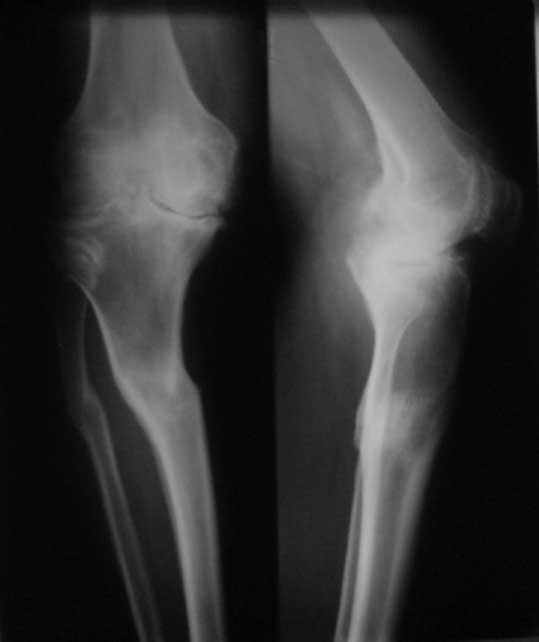

Пациент 8 мес после операции ТКА, в анамнезе неправильно сросшийся

перелом голени, коррекция оси (снимки прилагаются).

надежде на дальнейшую разработку. До эндопротезирования 40/10/0.

Причина нынешнего состояния, артрофиброз?

Какие действия следует предпринять, удаление рубцов,релиз головок 4-главой мышцы?